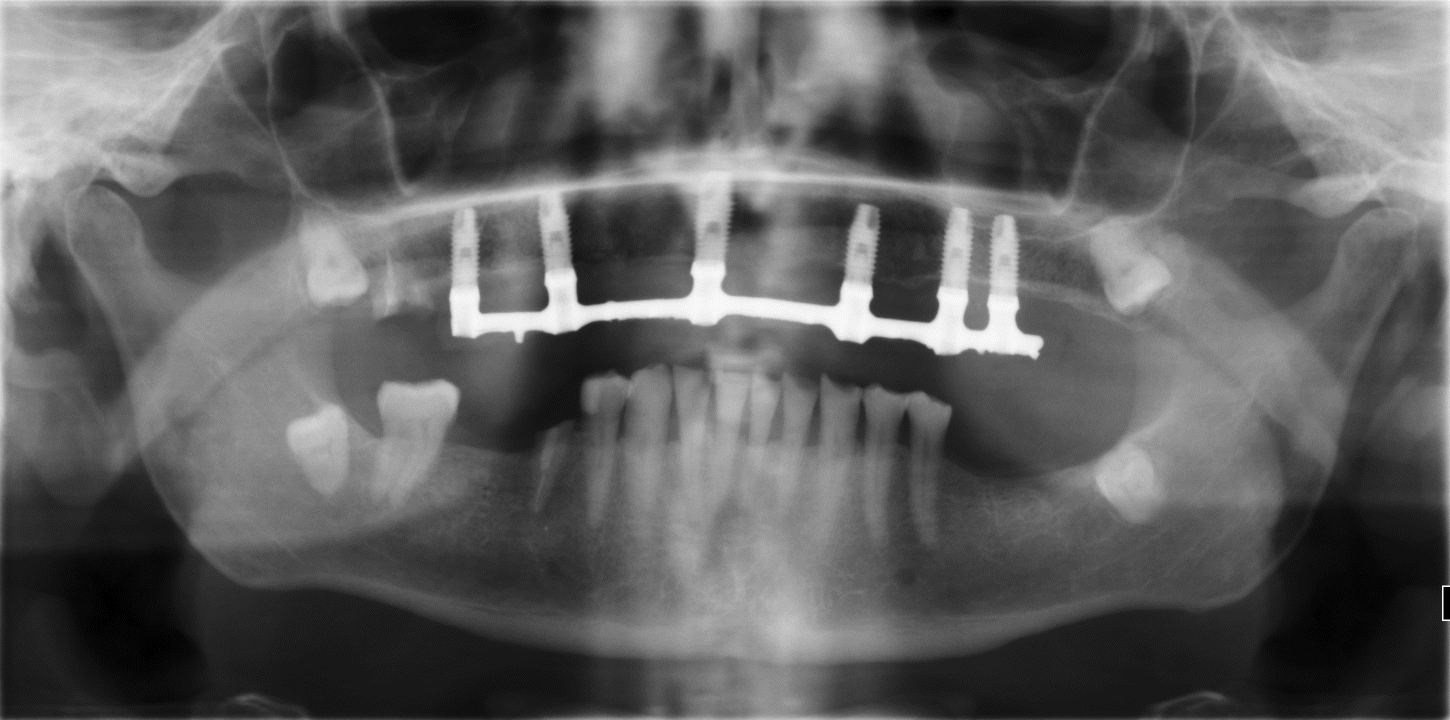

Buenos días, Adjunto enviamos RX panorámica y serie periapical superiores para identificar implantes en híbrida superior. Estamos especialmente interesados por la métrica del destornillador, porque tenemos que atornillar la misma [...]